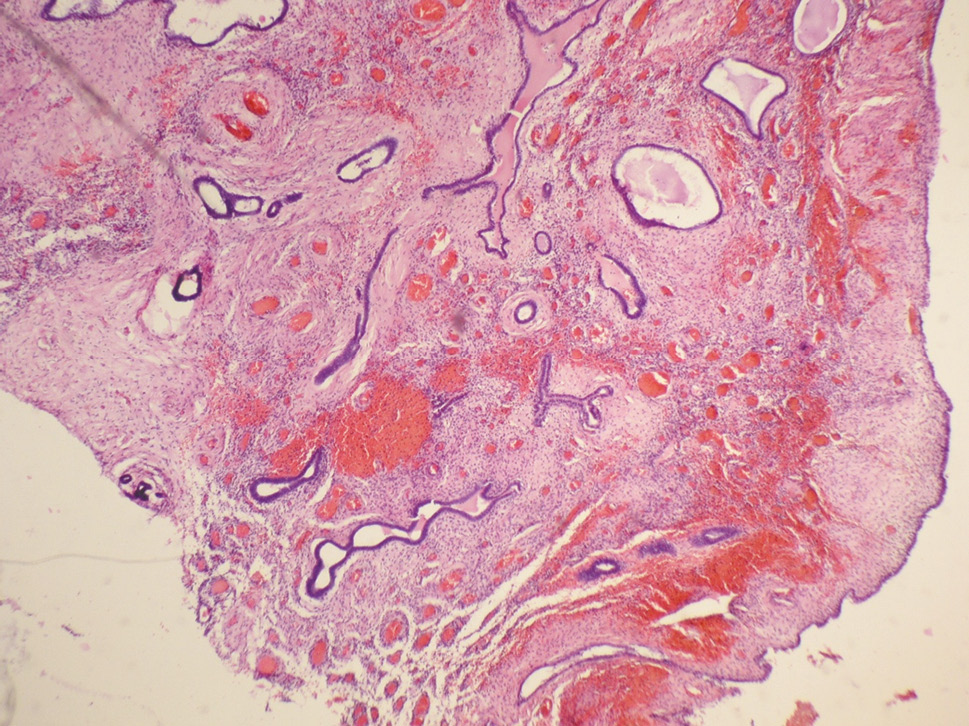

- Intrauterine synechia was hysteroscopically diagnosed in 8.6% of patients. These patients complained of infertility, miscarriage, and hypomenorrhea-type disorder of the ovarian-menstrual cycle. Regarding the prevalence and degree of obliteration of the uterine cavity, degree I of the prevalence of intrauterine synechia was established in 65.8% of cases (less than 1/4 of the volume of the uterine cavity was involved, the synechia was thin, easily destroyed by the hysteroscope body, the bottom and orifices of the tubes were free; the cords were pale pink, having the shape of a web with vessels located in them), while the degree II was revealed in 34.2% of cases (up to 3/4 of the volume of the uterine cavity was involved, there was no adhesion of the walls, single adhesions were not dense and were not been able to be destroyed by the hysteroscope body, isolated separate areas of the uterine cavity, the orifices of both uterine tubes were partially closed; the cords looked whitish, located on the side walls of the uterine cavity). Morphological research revealed that in 83.3% of cases, focal lymphoplasmacytic infiltration of the endometrial stroma, fibrosis, and endometrial atrophy of varying severity were identified, as well as neutrophilic granulocytes in some cases (Fig. 3).

Fig. 3. Fibrous adhesions with severe lymphoplasmocytic infiltration, surrounded by the endometrium with signs of chronic active inflammation (hematoxylin and eosin staining at ×100 magnification)

Рис. 3. Фиброзная ткань спайки с выраженной лимфоплазмоцитарной инфильтрацией в окружении эндометрия с признаками хронического активного воспаления (окраска гематоксилином и эозином, увеличение ×100)